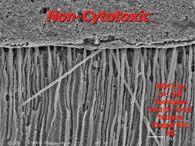

Change is a significant evolutionary tool provided it rests upon a solid and secure foundation. Innovations in materials and technologies occurring within the dental field are impacting powerfully on its art and science; however, dentistry, like all health care, is both a business and a profession. The pendulum swings that predicate trends and transitions within … Read more